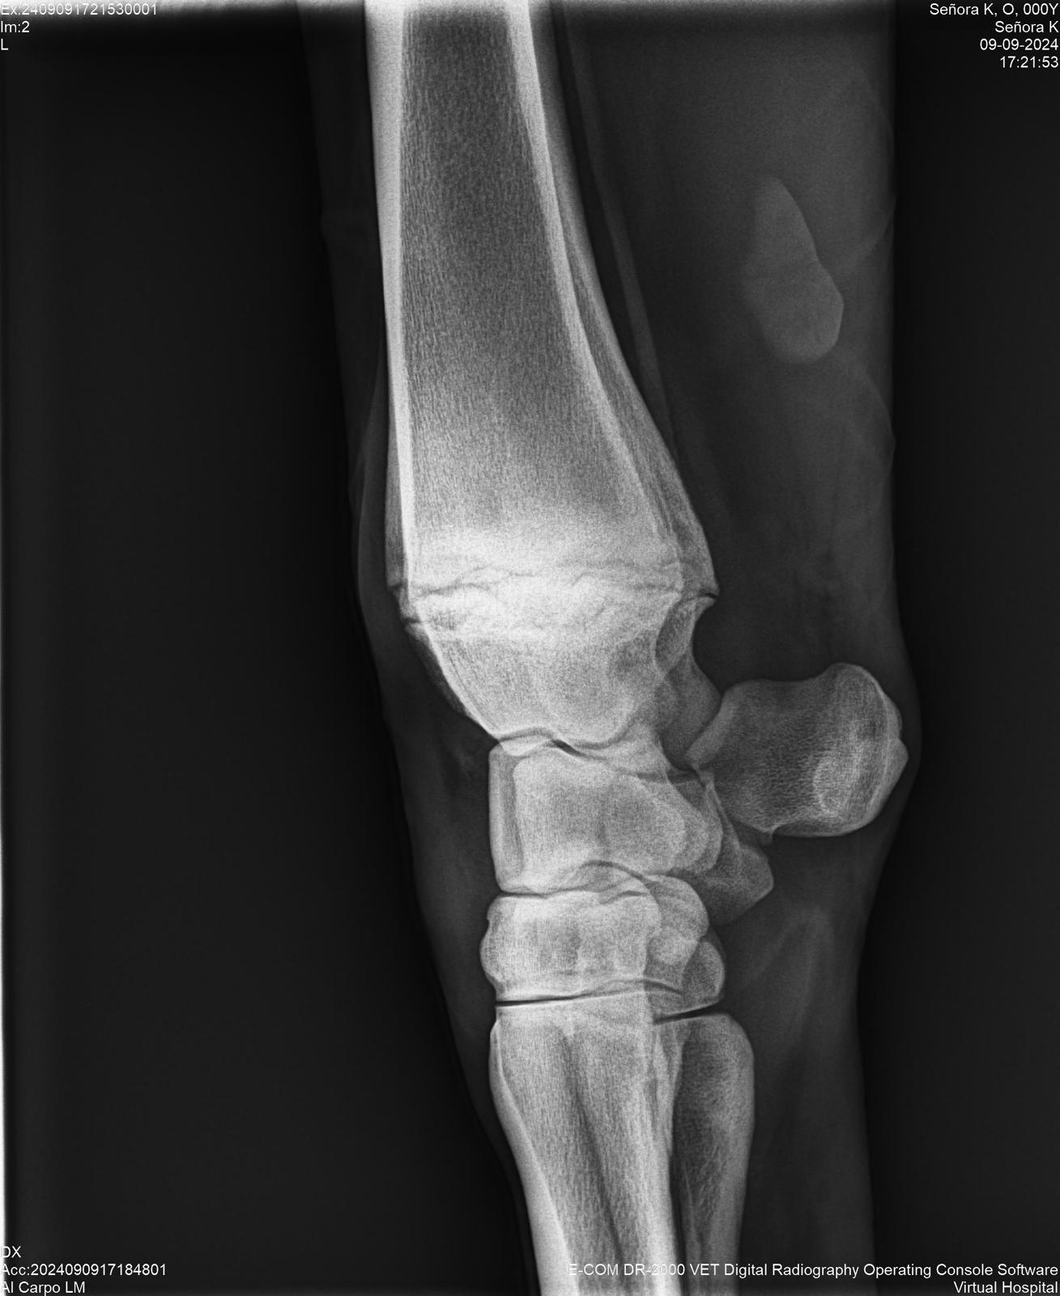

LOTE 44, SEÑORA K

Identificador: #291147-

Generacion 2022